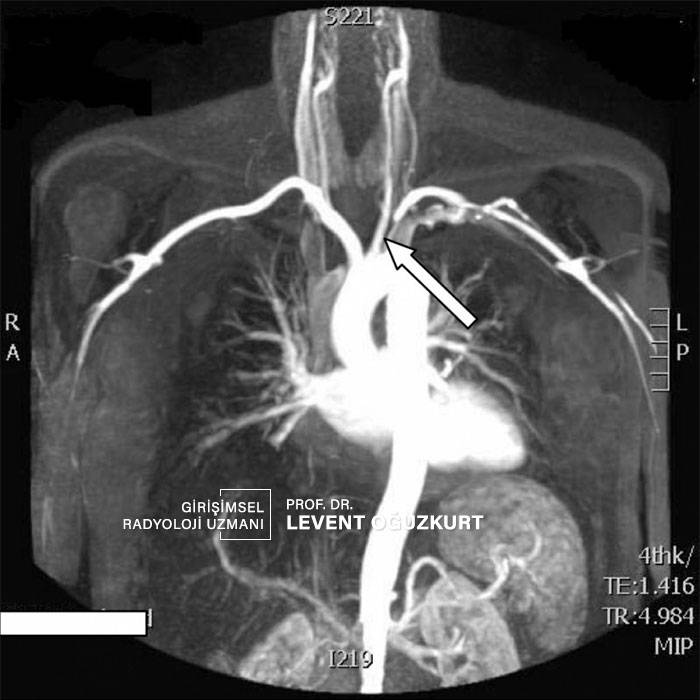

Kol atardamar darlığı en sık damar sertliği ya da damar kireçlenmesi (ateroskleroz) denen hastalığa bağlı oluşur. Takayasu hastalığı da sıklıkla kol ana damarında daralma ya da tıkanma yapar. Bunun dışında kalpten pıhtı atması (trombus atması ya da tromboemboli) ile de kol damarında ani tıkanma oluşabilir. Damar sertliği aylar ya da yıllar içinde olur ve yakınmalar yavaş yavaş gelişir. Kalpten pıhtı atması ile tıkanma ise anında ciddi yakınma yaratır ve acil tedavisi gerekir.

En sık yakınmalar kol ile bir iş yapıldığında kolda kolayca yorulma ve iş yaparken kolda ağrı olmasıdır. Özellikle kolu yukarı kaldırdığımız zaman (banyoda başımızı yıkarken, çamaşır asarken vs) yakınmalar çok daha belirgin olur. Bir özelliği kol damarı ciddi şekilde daralırsa ya da tıkanırsa o kolda tansiyon daha düşük çıkar. Eğer sağ ve sol kol tansiyonları arasında 20 den fazla fark varsa (örneğin tansiyon sağda 140, solda 115) bu genellikle kol damarında tıkanmaya bağlıdır. Bu hemen her zaman sol koldadır.

En önemli tanı yöntemleri radyolojik görüntüleme yöntemleridir. Öncelikle en kolay olan renkli Doppler ultrason inceleme yapılır. Ancak MR ya da bilgisayarlı tomografi ile yapılan anjiyografi tanıda daha değerlidir.

Ne zaman tedavi gerekir?

Kol damarında darlık miktarı %50'den fazlaysa ve o kolda iş yaparken yorulma, ağrı gibi yakınmalar oluşuyorsa tedavi önerilir. Tedavide günümüzde sadece anjiyografi ile tedavi yöntemleri kullanılmaktadır. Ameliyat sadece damar anjiyografi ile açılamazsa başvurulan bir tedavi yöntemidir. Ancak hemen her damar tıkanması anjiyografi ile açılır, açılamama ihtimali son derece düşüktür.

Kol damar tıkanıklığında anjiyografi ile tedavi nasıl bir yöntemdir?

Anjiyografi ile kol damarlarının açılması diğer bölgelerdeki damarların açılmalı ile hemen hemen aynıdır. Bu darlıklarda balondan çok stent yerleştirilmesi yöntemi kullanılır. Detaylı bilgi için anjiyografi ile tedavi bölümüne bakabilirsiniz.